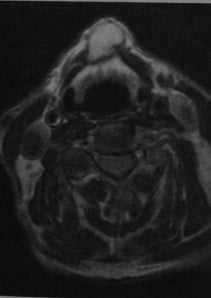

![Снимки МРТ и КТ. Щитовидно-язычная киста]()

Щитовидно-язычная киста. МРТ, Т2-взвешенное изображение: киста с четкими границами, расположенная сразу под подъязычной костью с гиперинтенсивным содержимым и гипоинтенсивной стенкой. Киста образует определяемую визуально выпуклость кожи.